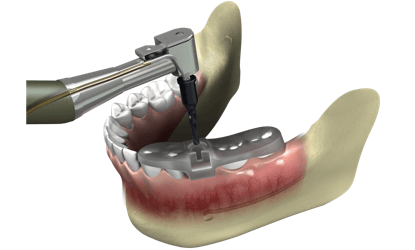

Virtualus 3D operacijos protokolas yra sukuriamas prieš implantaciją, implantacijos procedūra atliekama be pjūvių, todėl pacientas nejaučia skausmo nei operacijos metu, nei pooperaciniu laikotarpiu.

Dažniausiai, chirurginis gidas belopei chirurgijai yra spausdinamas 3D printeriu

Susisteminus informaciją, sumodeliuotas chirurginis gidas padeda išvengti minkštųjų audinių redukcijos.

Minimaliai invazyvi implantacija pasižymi mažesniu skausmu, tinimu ir greitesniu gijimu.

Individualus chirurginis gidas